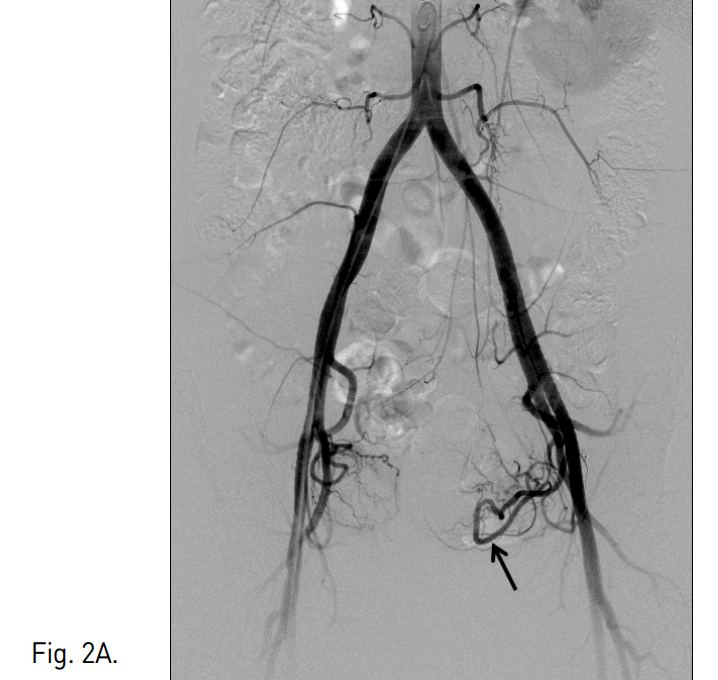

초음파 유도하에 우측 대퇴동맥을 천자하여 5F sheath(Terumo, Tokyo, Japan)를 삽입하였다. Pigtail 카테터(Cook, Bloonington, IN, USA)를 하부 대동맥에 위치시킨 후 골반조영술을 시행한 결과, 좌측 자궁동맥의 비대가 관찰되었다(Fig. 2a). 양측 자궁은 각각의 자궁 동맥으로부터 영양 공급을 받고 있었으며 두 동맥은 거의 서로 연결되어 있지 않았고 완전히 독림된 자궁이 조영되었다(Fig. 2b). 5 F Cobra 카테터(Cook, Bloonington, IN, USA)로 좌측 내장골동맥에 진입시키고 Microferret 카테터(Cook, Bloonington, IN, USA)로 좌측 자궁동맥을 선택하였다. 자궁동맥의 상행분절에 Microferret 카테터를 위치시키고 polyvinyl alcohol(PVA)(Contour, Bostonscientific, Fremint. Calif)을 이용하여 자궁동맥 색전술을 시행하였다. 150-250 micrometer, 250-355 micrometer, 355-500 micrometer의 PVA를 순서대로 사용하는 1-2-3 프로토콜로 색전술을 시행하였다. 이때 조영제와 식염수가 1:1로 섞인 용액에 PVA입자를 넣어서 총 60ml를 만들었는데, 각각의 사용한 양은 20cc( 1/3 vial), 40cc(2/3 vial), 20cc(1/3 vial) 이었다. 10 번의 심장박동 동안 자궁 동맥내에 조영제의 정체가 보일 때까지 색전술을 시행하였다. 우측 자궁동맥 조영술에서 좌측 자궁과 연결 되는 작은혈관이 관찰 되었으나 향후 체외수정을 고려하여 색전술을 시행하지 않았다(Fig. 3). 색전술 후 3개월째 시행한 MR에서 선근증 완전괴사를 관찰할 수 있었으며 좌측 자궁은 44.3%의 볼륨감소를 보였다(Fig. 4a-b). 시

Fig. 2

A, B. Pelvic aortogram shows tortous and dilated left uterine artery (arrow) and two separated uteruses (arrows and arrowheads in B).